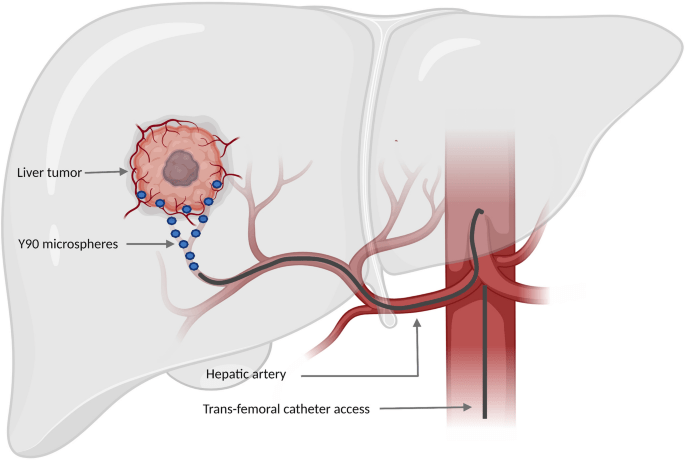

Quando o tumor é grande demais para ser considerada a possibilidade de transplante ou cirurgia, existe a possibilidade de reduzir o seu tamanho através de quimioembolização (TACE), que é um procedimento onde o radiologista intervencionista identifica a artéria que está nutrindo o tumor, injeta uma dose de quimioterápico direto na lesão e entope a artéria para “matar” o câncer. Apesar de ser considerado um tratamento paliativo ou como “ponte” para o transplante, também pode curar. Uma variação mais recente desse tratamento, que cada vez fazemos mais, é a radioembolização, onde ao invés de um quimioterápico injetamos microesferas radioativas.